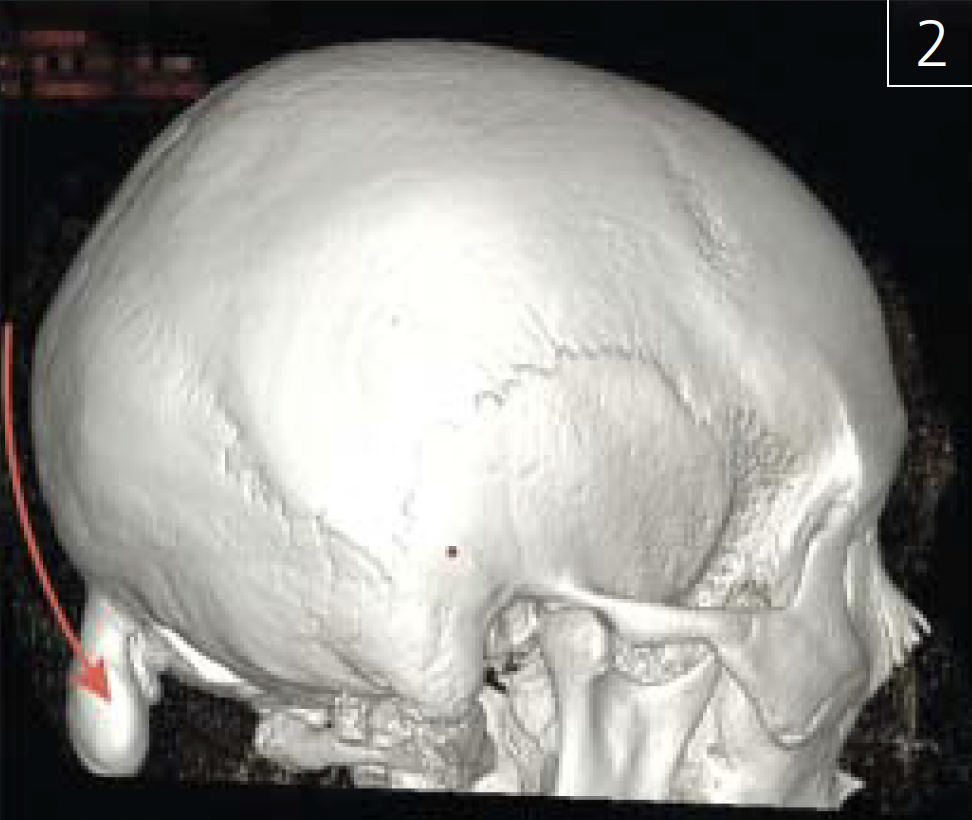

Патологическое новообразование может выступать симптомом первичной или вторичной опухоли костной ткани (рис. 2; 3 а-в),

Рис. 2. Остеома черепа(показана красной стрелкой), трехмернаяреконструкция МСКТ